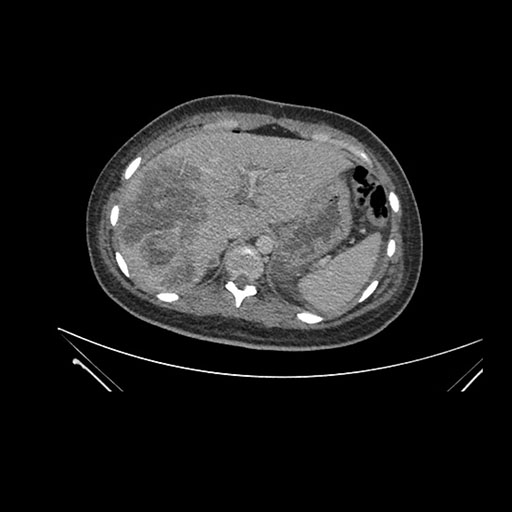

Axial Venous